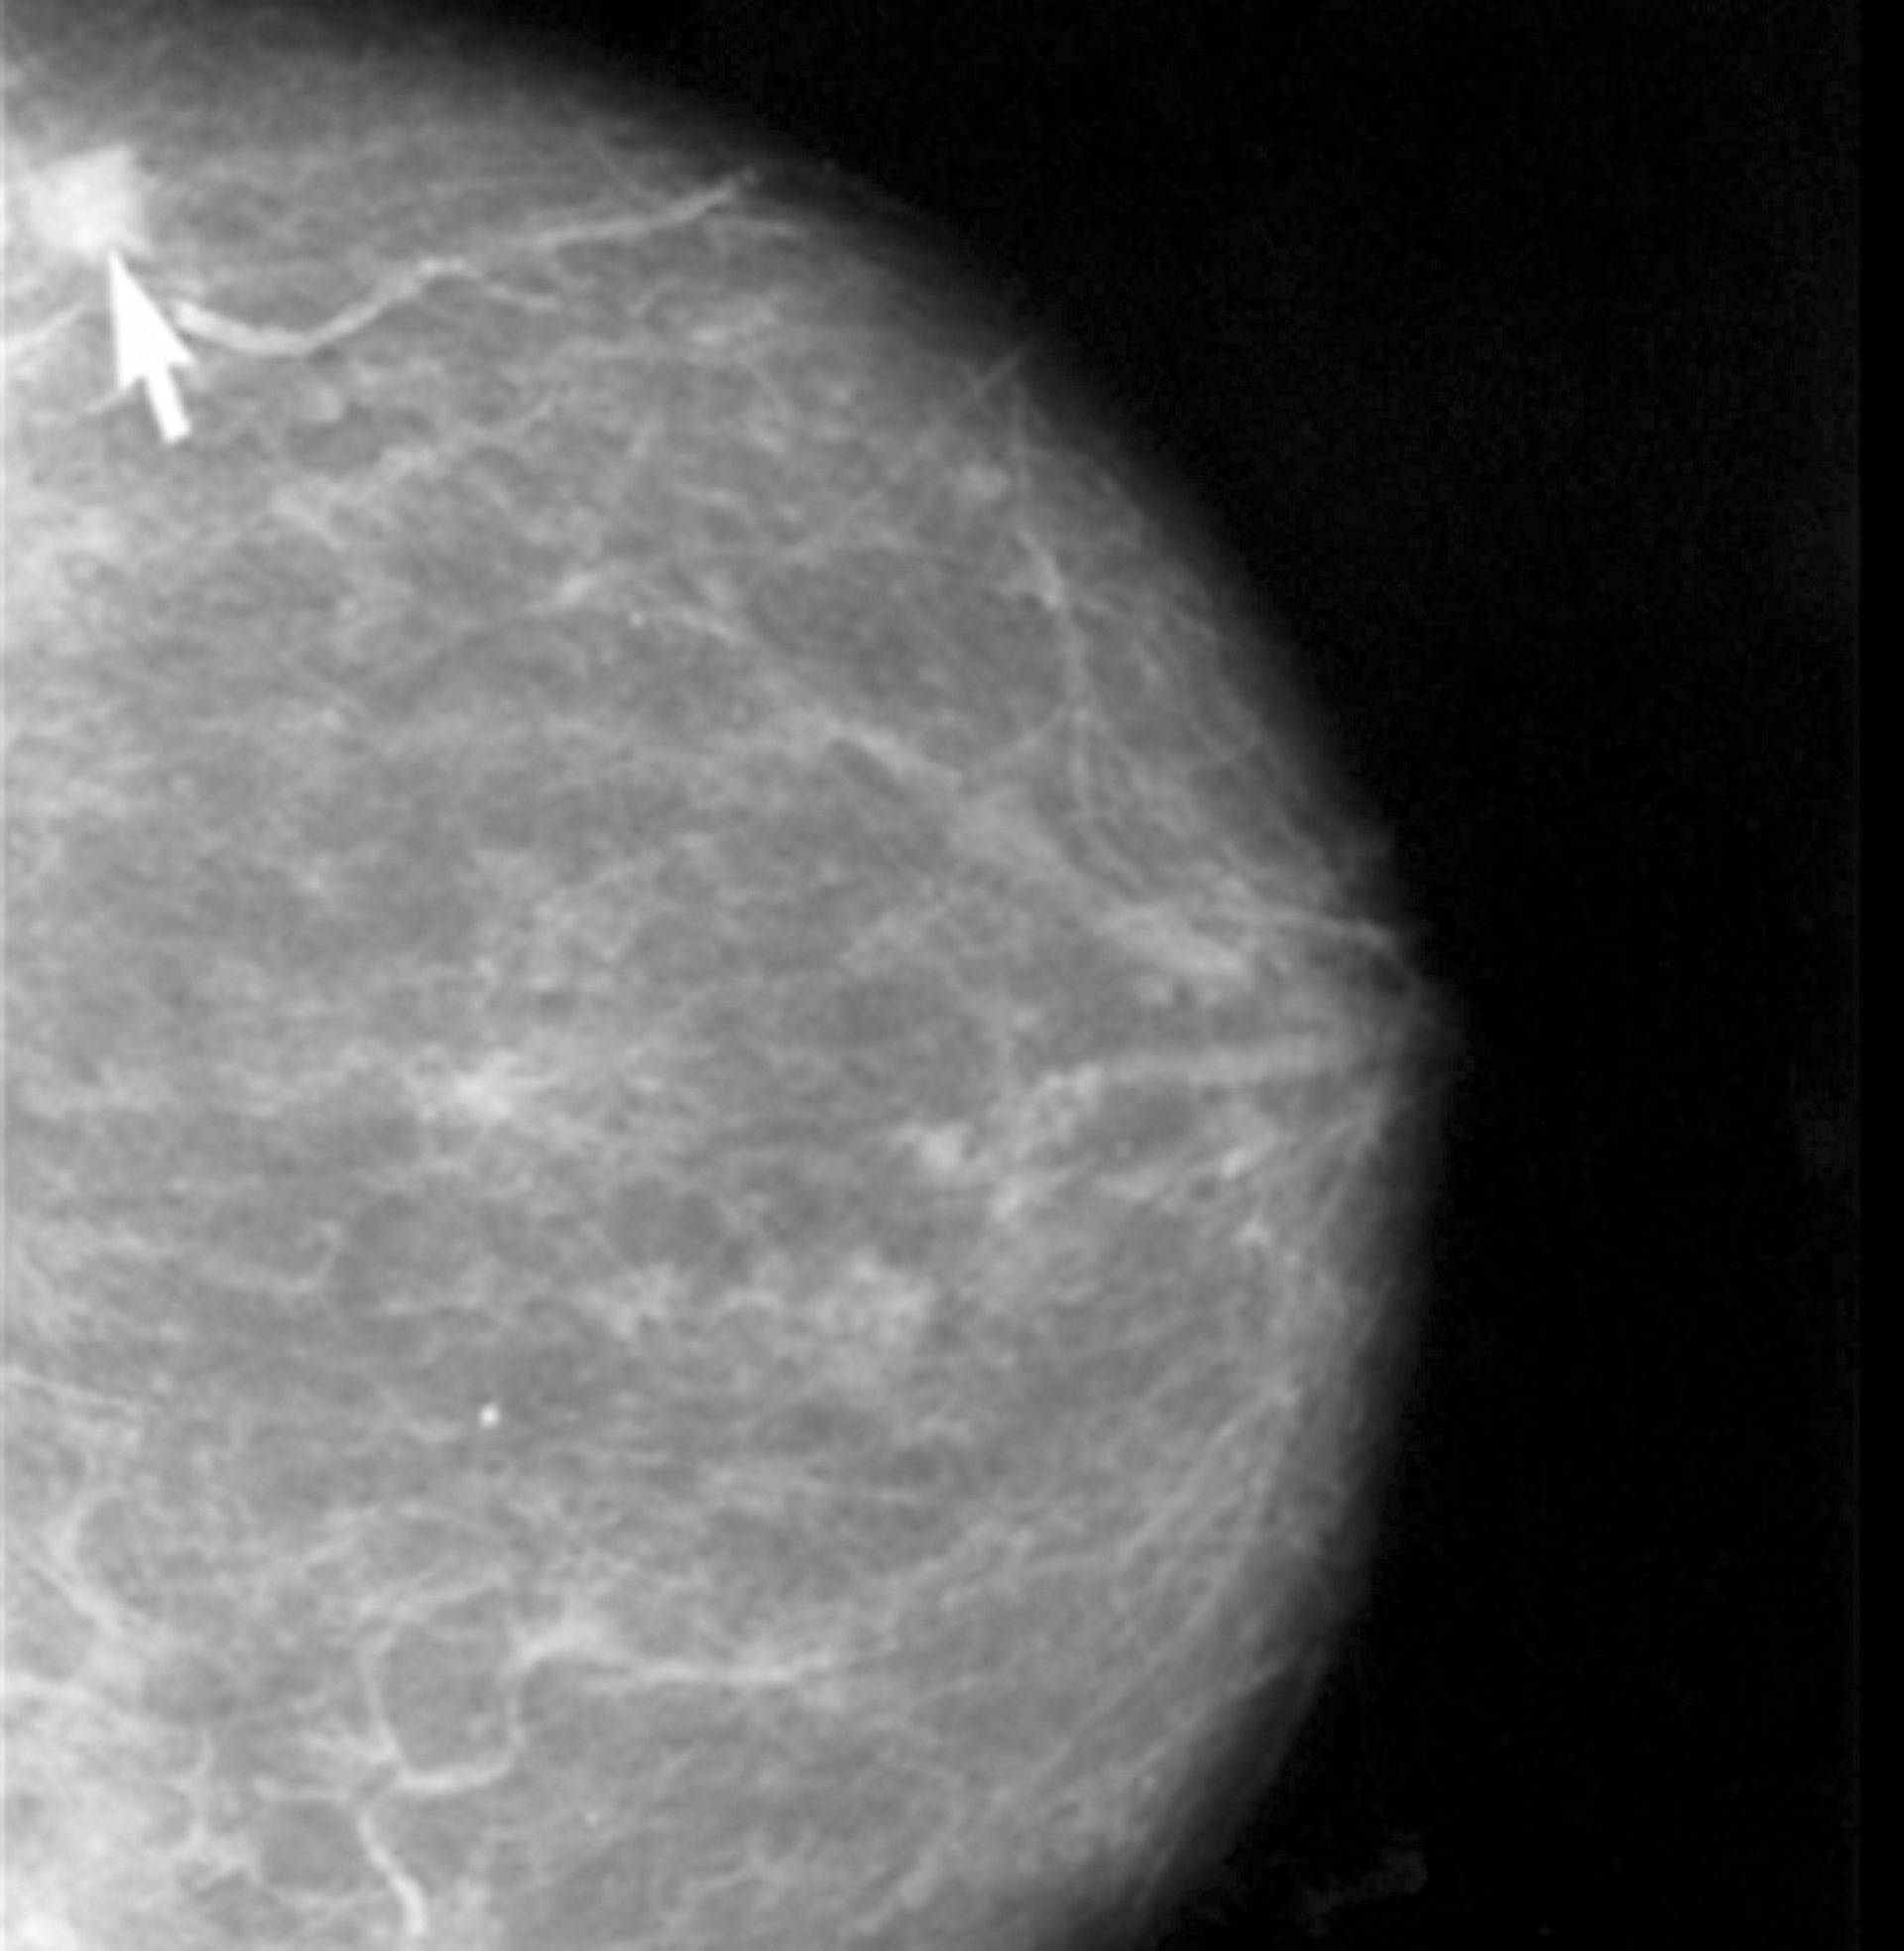

Diseñan nuevos nanodispositivos de liberación controlada de fármacos para terapias contra el cáncer de mama

Cáncer de Mama